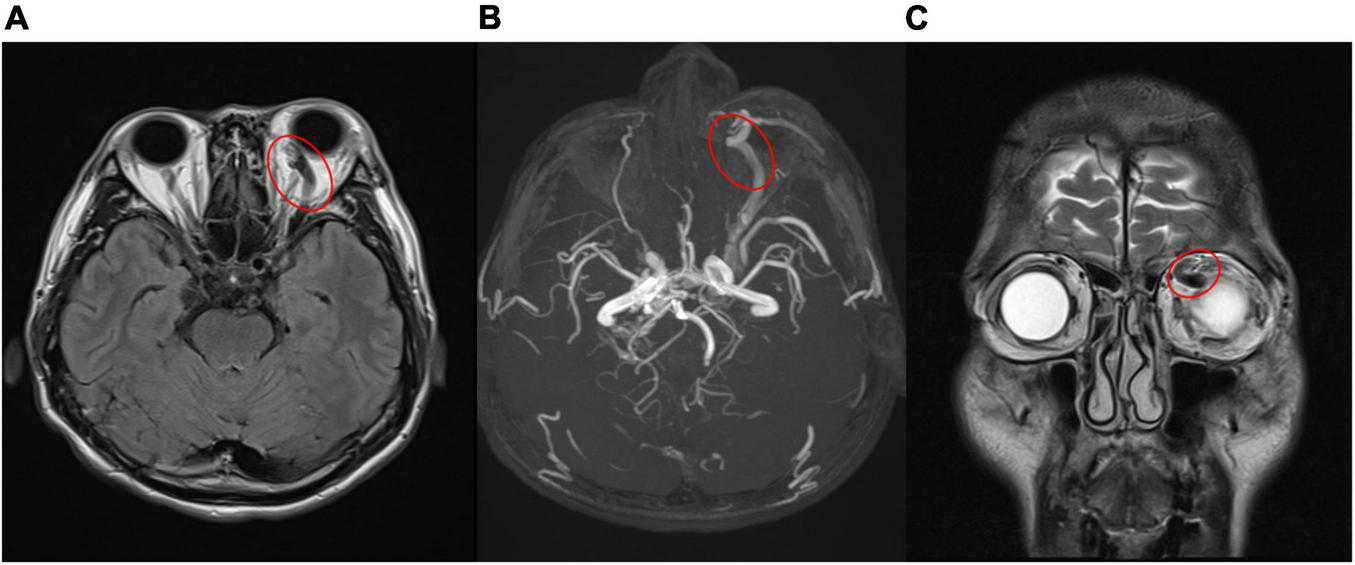

FIGURE 3

(A,B) Engorged left superior ophthalmic vein (red circle) in magnetic resonance imaging (A), magnetic resonance angiography (B), which confirmed carotid- cavernous sinus fistula. [(A) T2-weighted-Fluid-Attenuated Inversion Recovery, transverse view; (B) magnetic resonance angiography]. (C) Coronal view of magnetic resonance imaging revealed prominent engorged superior ophthalmic vein (red circle) [T2- Turbo spin echo (TSE) imaging, coronal view].